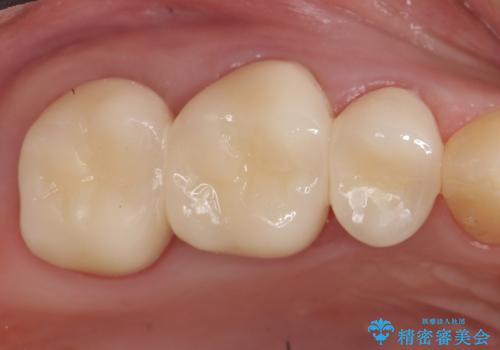

オールセラミッククラウン 根管治療 奥歯の補綴